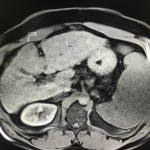

En el presente caso, encontramos una lesión típica de hepatocarcinoma en el segmento 5 ( hiperintensa en T2, restringe en la Difusión con ADC bajo. Realza heterogéneamente postcontraste EV, con wash out y presencia cápsula tardía).

El objetivo es identificar dentro de la multifocalidad de nódulos , un hepatocarcinoma precoz o de pequeño tamaño , cuando la posibilidad de tratamiento con intención curativa es viable , a pesar de la cirrosis.